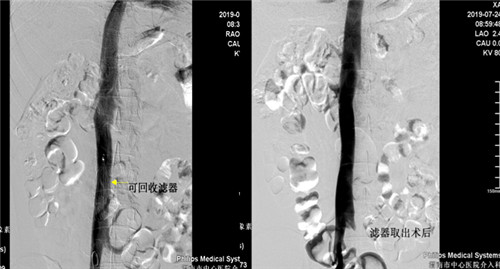

患者是一年轻男性,半年前因高血压性脑出血住院治疗,发现左下肢髂静脉股静脉腘静脉胫后胫前静脉血栓形成,由于脑出血有抗凝溶栓禁忌症,为预防肺栓塞的发生急诊行下腔静脉滤器(可回收)植入术,患者无脑出血后进行规范抗凝再无出血,超声复查下肢静脉血管未见新鲜血栓,D-二聚体正常,于7月24日早八点行经颈静脉下腔静脉滤器取出术,术后患者无腹痛发热出血等症状。

目前市中心医院对于下肢深静脉血栓形成患者常采用DENALI可回收下腔静脉滤器(最长回收时间窗632天)置入术预防肺栓塞的发生,该手术已在乐鱼在线登录入口广泛开展。但下腔静脉滤器取出术在渭南区域内尚未开展,市中心医院首次成功取出DENALI可回收下腔静脉滤器,标志着因担心滤器永久置入发生并发症而纠结放与不放的时代已结束,亦开创了渭南市血管介入新篇章,更好地为各科室的临床工作保驾护航,为更多的患者带来福音。